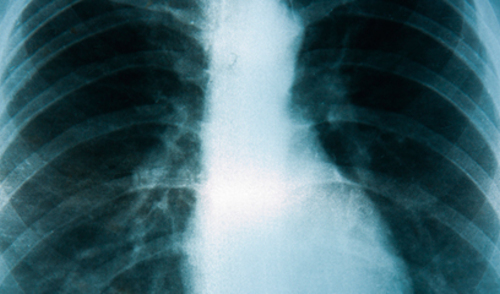

Kronična opstuktivna plućna bolest (KOPB)  naziv je za bolesti koje smo prije nazivali kronični bronhitis i emfizem i riječ je o jednoj od najslabije prepoznatih bolesti i najmanje dijagnosticiranih u svijetu.

KOPB se dijagnosticira spirometrijom, jednostavnom neinvazivnom metodom mjerenja plućne funkcije s pomoću elektronskog uređaja. Liječenje KOPB-a je kompleksno i uključuje brojne mjere - prestanak pušenja, redovito uzimanje lijekova, ali i ostale nefarmakološke mjere poput plućne rehabilitacije, liječenja kisikom te transplantacija pluća.